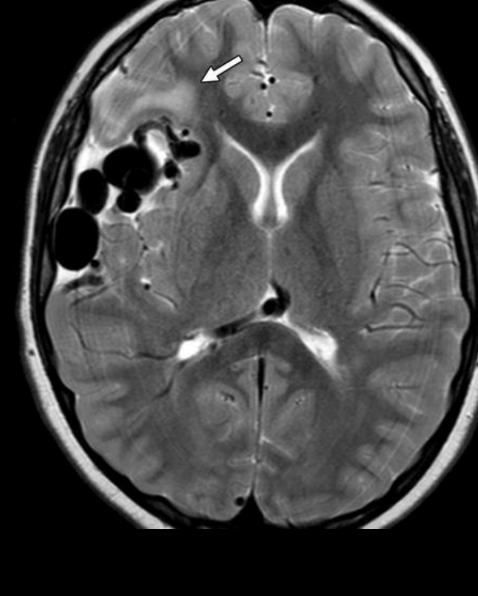

A

RM